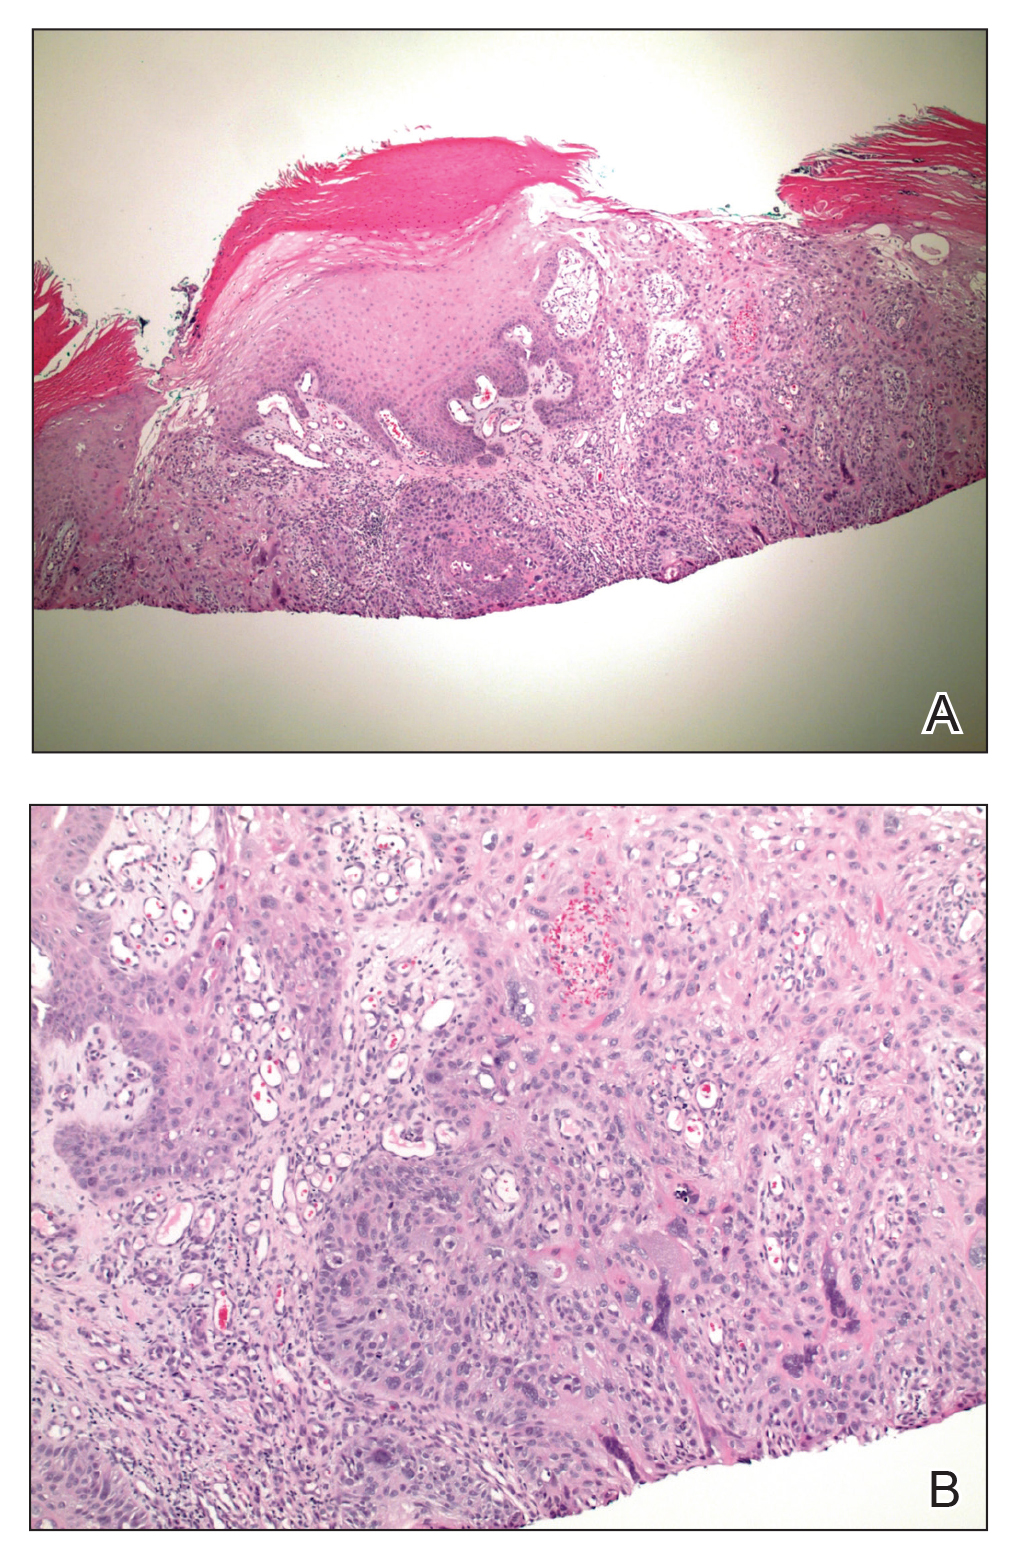

Figure 2. Invasive squamous cell carcinoma. A, Histopathology demonstrated an atypical proliferation of keratinizing epithelial cells extending from the epidermis and discontinuously into the dermis. Nuclear pleomorphism was noted (H&E, original magnification ×40). B, Dilated superficial dermal blood vessels represented possible background changes observed in erythema ab igne (H&E, original magnification ×100).